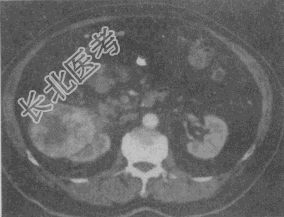

- 单项选择题患者,男, 51岁。右肾区不适4个月余,有镜下血尿。CT扫描结果见图。最有可能的诊断是

A、肾癌

B、肾盂癌

C、肾错构瘤

D、肾结核

E、肾腺瘤